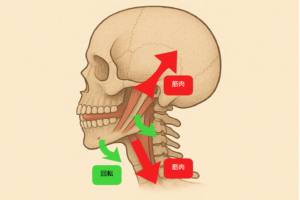

そしてこの下顎の後方回転(後退)を助けているのは

このように「後むきの」筋肉たちなのです(PTさんはこの辺り詳しいと思います)

本来MRC矯正は顔(あご)を前に向かって成長させて気道を大きくしたいのですから、これでは真逆の力が加わることになりますね。。。。